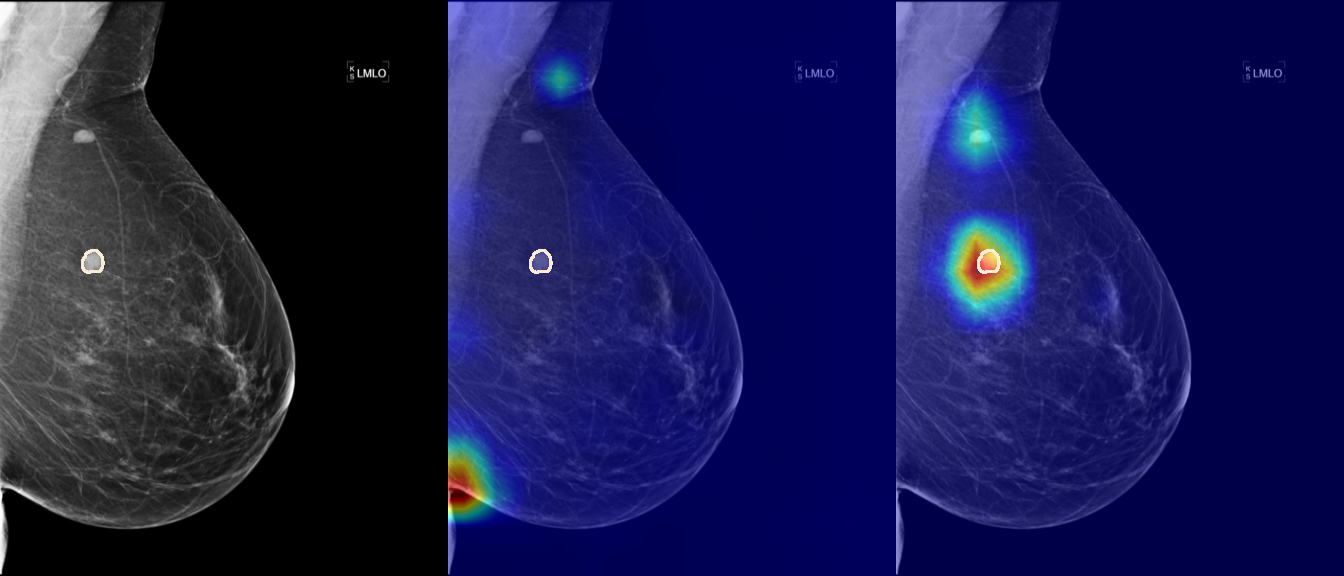

To interpret the decision-making process behind the quantitative results, we visualized Class Activation Maps (CAM) for the top-performing methods, ERM and VREx. Figures 1 through 2 illustrate discriminative regions identified by the models within the full mammograms.

Localization of Clinical Features: A key concern in medical AI is whether high performance stems from genuine pathology detection or spurious background correlations. Our visualizations suggest that Standard ERM achieves its superior quantitative performance by predominantly prioritizing clinical cues. As shown in the top rows of the Figure 1 and Figure 2, the ERM-trained models consistently focus attention on the specific lesion regions within the breast tissue. This demonstrates that despite lacking explicit invariance constraints, ERM is capable of learning robust, medically relevant features when trained on diverse multi-source data.

Attention Drift in Both Methods: While both ERM and VREx generally identify the correct region of interest in successful cases, neither method is immune to attention drift. We observe instances in both training paradigms where the model focuses on irrelevant areas, such as healthy fibroglandular tissue or background artifacts (e.g., rows 5 and 6 in Figure 1). This indicates that while VREx is designed to penalize instability, it does not guarantee perfect anatomical focus compared to the unconstrained ERM baseline.